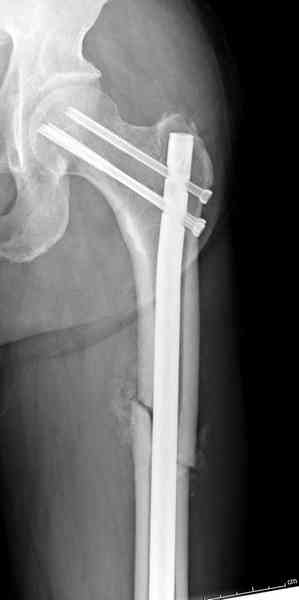

В первый же день произведено антеградное штифтованием DePuy Trochanteric Nail.

На второй день (7) обнаружен пропущенный перелом,

сделаны Компьютерная Томограмма

и проведены шурурпы через и спереди штифта без удаления.

Послеоперационные снимки